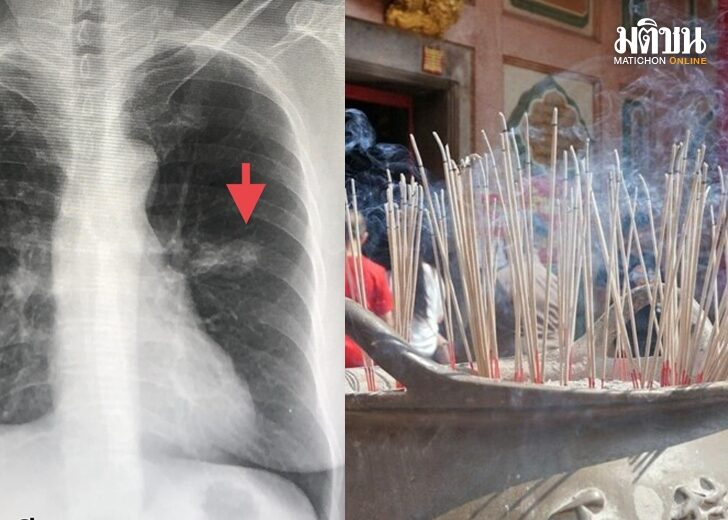

医生:没吸烟无二手烟伤害 连6年烧20根香 妇人患肺癌

近日马努医生遇见了一位患者,该患者之前从来没有过吸烟的经歷,也没有遭到二手烟的伤害,但是却患了肺癌。马努医生指出,肺癌是常见的癌症,如果在早期(1-2期)被发现,能够通过手术治愈。一位65岁的女性患者,7年前,每年都会做日常体检和肺部X光片,在左边肺部的上方发现一个肿块,一年之后肿块长大,才来再次就诊。患者没有任何的症状,不咳嗽、发烧、不会疲惫、没有胸痛、体重也没有下降,有高血压但是不吸烟。但患者有个习惯,就是每周四都会在上班处点上20根香,持续了6年之久。(泰国世界日报)